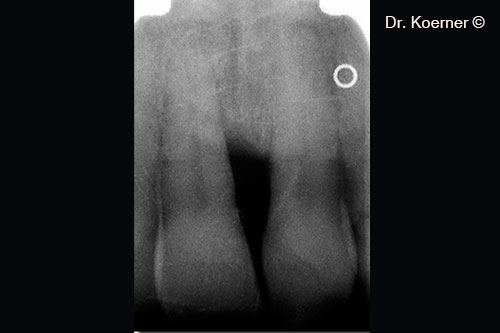

Tình trạng chụp X-quang 4 tháng sau phẫu thuật với nẹp cố định.

Tình trạng chụp X-quang 10 năm sau phẫu thuật.